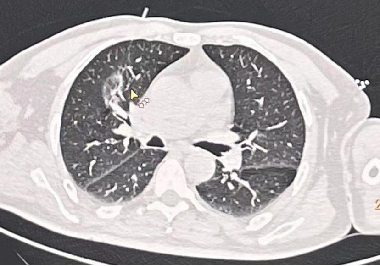

本次患者为63岁男性,健康体检时发现右肺上叶支气管血管束旁部分实性结节,最大径11mm,结节内部可见少许实性成分及血管穿行,边缘深分叶,具备一定的恶性征象,适合进行消融治疗。术前,邱教授团队林老师与患者及家属进行了谈话与充分告知。术中在CT引导下,调整进针角度与深度,穿刺针顺利到达满意位置,经40w、7min热消融后,病灶周围如期出现“煎蛋征”。当病灶周围磨玻璃影达到10mm时,停止消融,使用明胶海绵对针道进行处理,治疗结束。术后CT实时观测患者肺部情况,未见气胸、出血等并发症,患者安全返回病房。术后第二天,患者复查胸片后未见胸腔积液、气胸等并发症,顺利出院。术后1月、3月、6月放射科将对患者进行随访,时刻关注患者病情的变化。

病灶周围如期出现“煎蛋征”